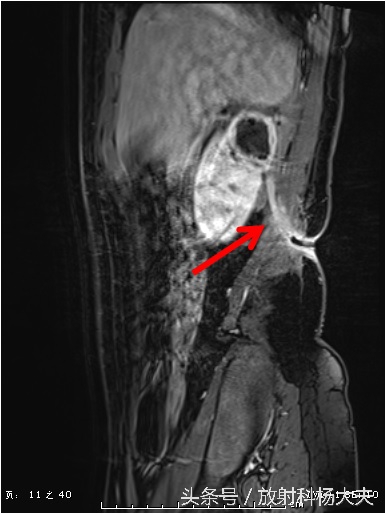

这个囊性病变到底是什么?囊性肿瘤?有无办法继续明确呢?有!那就是MRI,除了进一步明确,还能更清楚的显示窦道的走行。下图这个序列,叫DWI,红箭所示的白白的东西,证明这是一个脓肿!

终于搞清楚了,原来一个月前的腰痛,是肾脏的脓肿,并且MRI上还能清晰的显示脓肿破口的位置,下图中黄箭所示(红箭为脓肿)。

还有那弯曲的窦道。